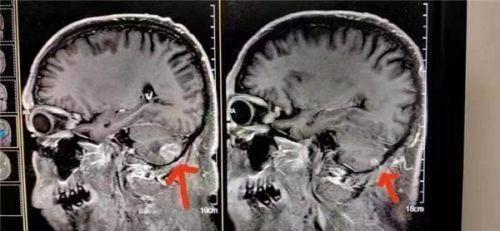

患者在北京301医院检查治疗结果左脑肿瘤大于右脑肿瘤,陈海林采取采取纯中药的临床治疗,经三个月的治疗,于2023年6月28日的颅脑磁共振平扫十增强:1:右侧小脑转移瘤复查与2o23年3月9日MR片对比,病变基本消失。这个结果连301医院的都声称是奇迹。Case 24: Small cell lung cancer with brain metastasis

The patient underwent examination and treatment at Beijing 301 Hospital, and the results showed that the left brain tumor was larger than the right brain tumor. Chen Hailin adopted clinical treatment with pure Chinese medicine, and after three months of treatment, on June 28, 2023, the brain magnetic resonance plain scan with ten contrasts: 1. Compared with the MR film on March 9, 2023, the right cerebellar metastatic tumor reexamined and the lesion basically disappeared. This result is even claimed to be a miracle by Hospital 301.